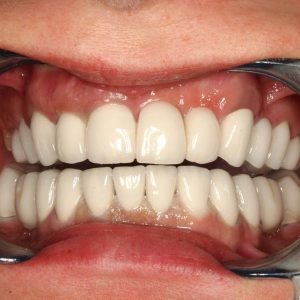

A végeredmény, a frontfogak a belső oldalon összesínezve